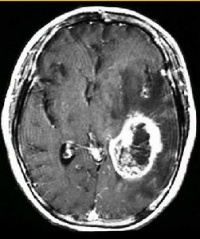

(2)CT及MRI扫描:CT表现为瘤体呈等密度或低密度,少数呈高密度影像。肿瘤多为圆形或不规则形,位于内听道口区,增强效应明显。MRIT1加权像上呈略低或等信号,在T2加权像上呈高信号。第四脑室受压变形,脑干及小脑亦变形移位。注射造影剂后瘤实质部分明显均一强化,囊变区不强化。

(3)CT及MRI检查:目前听神经鞘瘤诊断的标准是Gd-DTDA增强的MRI,特别是当肿瘤很小(<1cm)或在内听道内,CT扫描阴性又高度怀疑肿瘤存在时应该进行GD-DTPA增强的MRI。CT与MRI两种检查有相辅相成的作用,如CT发现有病侧内听道扩大时,增强CT可发现肿瘤对于估计中颅窝入路时颞骨的气化程度及高颈静脉球与后半规管及底的距离有帮助。如果病人已作了CT而肿瘤较大,MRI可提供对脑干压迫的范围Ⅳ脑室是否通畅脑积水、是否存在的情况对可疑听神经鞘瘤或CT检查难于确定时,全序列的MRI可做出鉴别诊断。但也要注意Gd-DTPA的可能假阳性,这与内听道内神经的炎症或蛛网膜炎有关;任何小的接近底部的增强病变应该在六月后作MRI复查,以评估其生长情况。